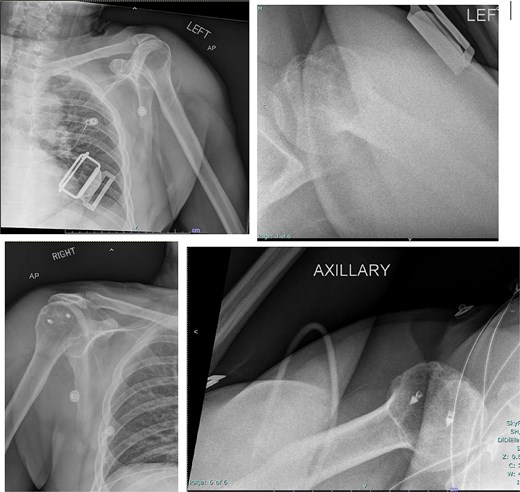

A 59-year-old right-hand–dominant male with history of prior right rotator cuff repair presented to the emergency department after a workplace injury in which four 60-lb pallets fell onto his upper back, while he was operating the steering wheel of a pallet jack. He arrived with both upper extremities locked in overhead abduction, reporting bilateral shoulder pain and hand paresthesias (Fig. 1).

Both shoulders were reduced urgently by the orthopedic team, with immediate improvement in paresthesias (Fig. 2). Post-reduction CTs were significant for bilateral chronic rotator cuff disease with superior migration of the humeral heads, right-sided supraspinatus and subscapularis atrophy, and a left nondisplaced glenoid fracture (Figs 3 and 4). He was discharged home in bilateral slings.

Post-reduction X-rays demonstrating congruency restored to right and left glenohumeral joints, with evidence of superior humeral head migration bilaterally.